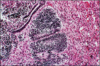

Ovarian tumor that occurs typically postmenopause. Cuboidal granulosa cells in cords, sheets with spindle or plump, lipid-laden theca cells. Granulosa cells may form Call-Exner bodies (shown), recapitulating ovarian follicles. These show coffee bean nuclei with folds/grooves. +Inhibin

Increased estrogen causes precocious puberty and predisposes patient to endometrial and breast cancers

Granulosa cell tumors, adult ype

Tumor marker for granulosa cell tumors

Inhibin

____ bodies formed in granulosa cell tumors.

Call-Exner